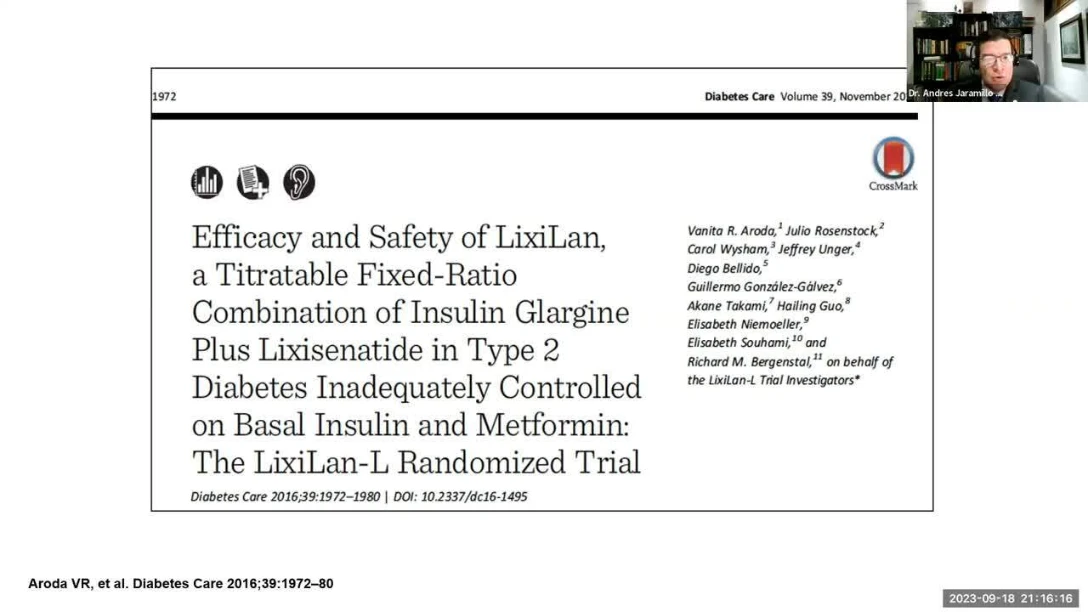

Descubra la más reciente actualización sobre la evidencia científica y los datos basados en la vida real que se han recopilado en el campo de la epidemiología. Esta información incluye detalles sobre la carga que estas enfermedades imponen a las personas y a la sociedad en general, así como los métodos de control que se están implementando para hacer frente a estas situaciones.

También se aborda el impacto económico que tienen enfermedades como asma grave, cardiovascular, dermatitis atópica, diabetes o enfermedades raras, etc., en la vida de nuestra población. Estos elementos son fundamentales para comprender la magnitud del problema y para desarrollar estrategias efectivas que ayuden a mejorar la salud pública.